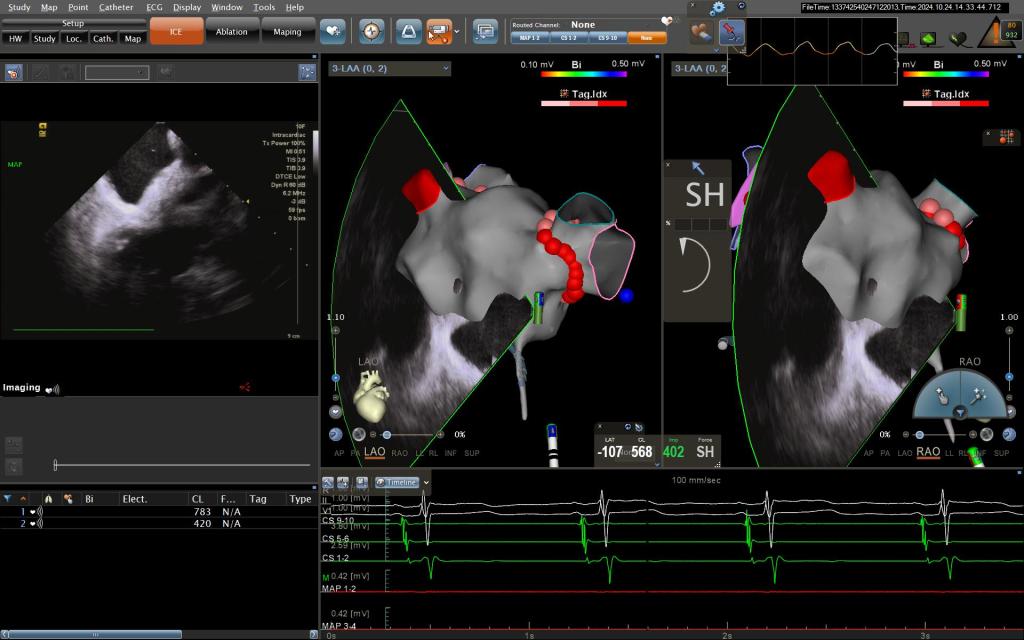

手术过程中,王洪涛教授亲自操刀,充分利用CARTO 3三维标测系统,实现了精准定位和消融,成功为患者实施了房颤射频消融术。随后,团队又克服了镜面右位心带来的操作困难,使用新一代国产左心耳封堵器LACbes成功完成了左心耳封堵术,有效预防了卒中的发生。王洪涛教授解释:“房颤射频消融术能够消除房颤的症状,而左心耳封堵术则能够闭合房颤患者血栓发生的根源部位,两者结合能够大大降低患者的卒中和出血风险。”